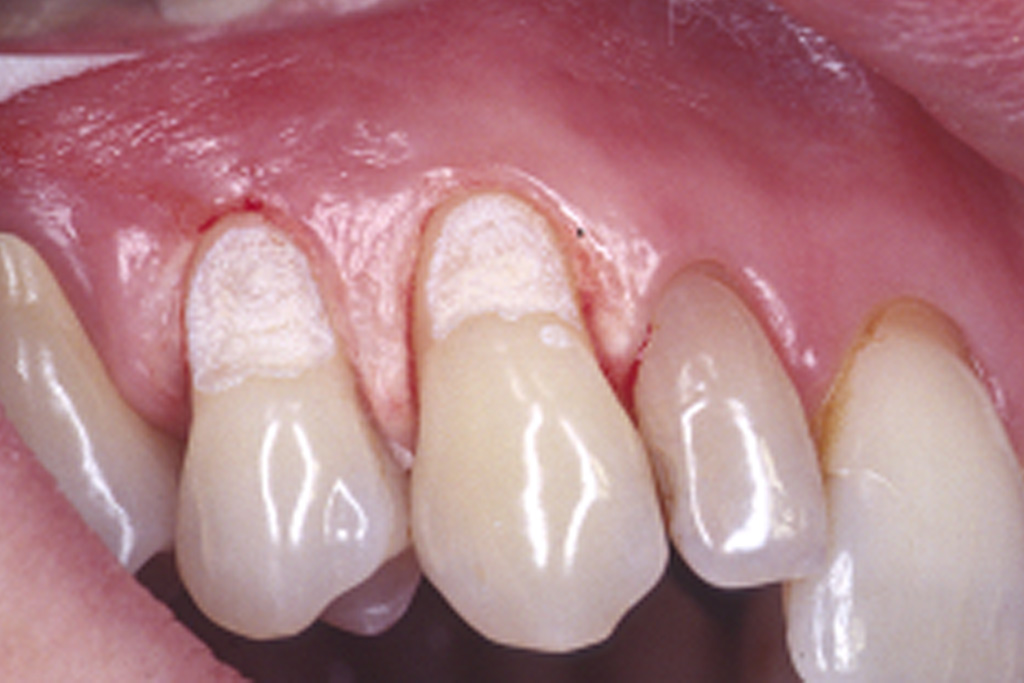

Die präzise Darstellung präparierter Zahnstümpfe auf dem zahntechnischen Meistermodell stellt auch heute noch eine der wichtigsten Schnittstellen zwischen Zahnarzt und Zahntechniker dar. In der Produktionskette hin zur fertigen Krone nimmt dabei der Zahnarzt eine entscheidende Schlüsselstellung ein. Nur er kann durch seine reproduzierbare und präzise Abformmethodik die Voraussetzung für ein perfektes Modell schaffen und damit Passungenauigkeiten der anzufertigenden Krone vermeiden. Dies ist besonders deshalb wichtig, weil Passungenauigkeiten an Kronenrestaurationen (Über- und Unterextension des Kronenrandes, übergroßer Randspalt ) häufig eine Fülle perioprothetischer und ästhetischer Probleme verursachen (Abb.1 ) :

Da die Präparationsgrenze bzw. der Präparationsrand in der Regel 0,5 bis 1,5 mm unterhalb des Zahnfleischrandes (= subgingival ) verläuft, wird zumeist während der Präparation des Zahnes das Zahnfleisch verletzt. In der Folge tritt eine verstärkte Blutung am Zahnfleischrand (= Sulkus) auf.

Bei der anschließenden Abformung der präparierten Zahnstümpfe bestehen zwei Probleme (Abb2.) . Zum Einen muss das den Zahn umgebende Weichgewebe vom Präparationsrand abgedrängt werden (= Retraktion) und zum Anderen darf während der Abformung kein Blut auf die abzuformende Zahnoberfläche gelangen. Unzureichende Retraktion und Blutungen im Sulkus verhindern eine präzise Abformung. Die Abformung muss wiederholt werden.

Mit Hilfe des Lasers können heute erstmals diese beiden. Hauptprobleme bestmöglich in den Griff bekommen werden.

Der Laser verdampft punktuell störende Gewebeanteile im Sulkus und stoppt gleichzeitig durch seine blutungsstillende Wirkung die Gewebeblutung . Dabei ist die Gewebeschädigung (=Trauma) minimal. Durch diese minimaltraumatisierende Wirkung ist die anschließende Wundheilung wesentlich schmerzärmer als bei der früher üblichen elektrochirurgischen Abtragung. Im Zuge der Heilung ist die Schrumpfungstendenz des Zahnfleischrandes zudem erheblich geringer. Dies fördert das ästhetische Erscheinungsbild der eingegliederten Krone im Zahnhalsbereich, da der Kronenrandbereich unterhalb des Zahnfleischrandes verbleibt (Abb. 3 ).

im Bereich der Vollkeramikkronen an den Oberkieferfrontzähnen 13-23